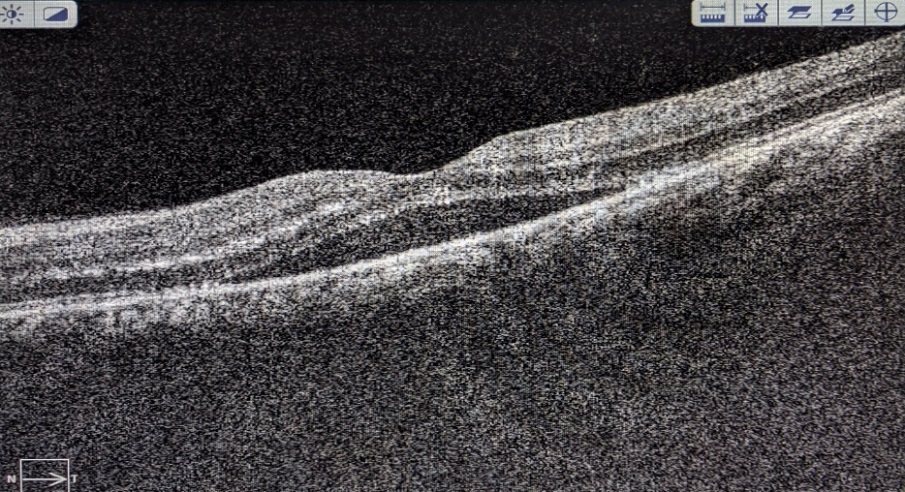

Typhoid fever affecting the eye has been reported as early as 1893 [2] Practically every layer of the eye can be affected. The role of typhoid fever in causing immune mediated retinitis has recently spiked interest in the ophthalmology community. The clinical features are similar to the other PFR sequelae described in patients who are immunocompetent and have had fever prior to the onset of ocular symptoms. Typhoid fever and its ocular manifestations can be described during acute stages of the disease or post-fever stages. During acute stages the patient can present with catarrhal conjunctivitis, ulcerative keratitis, keratomalacia, iridocyclitis, choroiditis, vitritis and optic neuritis and optic atrophy paresis of accommodation ptosis and abducens nerve palsy. Post-fever ocular signs described include focal or multifocal retinitis, with or without stellate maculopathy, vasculitis and, retinal venous occlusion due to vasculitis resulting in intraretinal haemorrhages's, cotton wool spots and retinal and optic nerve head edema, neuroretinitis, large neurosensory detachment, retinal detachment, frosted branch angiitis, pseudoretinitis pigmentosa, endophthalmitis, panophthalmitis, orbital cellulitis and tendonitis.[1], [2], [3], [4], [5], [6], [7] OCT may show hyperreflectivity in the inner retinal layers corresponding to the area of retinitis.

In our study, BCVA of left eye improved from 6/36 to 6/6(Figure 6). Left eye fundus, OCT and FFA were noted to be normal in comparison to a study Acharya P et al[22] who found in their study post‑treatment visual acuity in one series ranged between 6/60 to 6/12 in most of the cases and the fundus lesions almost resolved leaving retinal pigment epithelial changes and foveal thinning in cases with severe macular involvement.